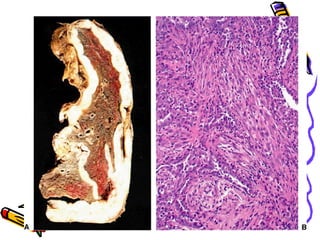

Morphology

• Diffuse pulmonary interstitial

fibrosis

• Begins in the lower lobes &

subpleurally (silica &CWP >upper)

• Honeycomb lung

• Pleural plaques

Microscopy

• Interstitial fibrosis around respiratory

bronchioles and alveolar ducts, involves

adjacent alveoli

• Asbestos bodies –golden brown fusiform

or beaded rods with a tranluscent centre

(asbestos fibre coated by iron containing

proteinaceous material)

• Trapping & narrowing of pulmonary

arteries